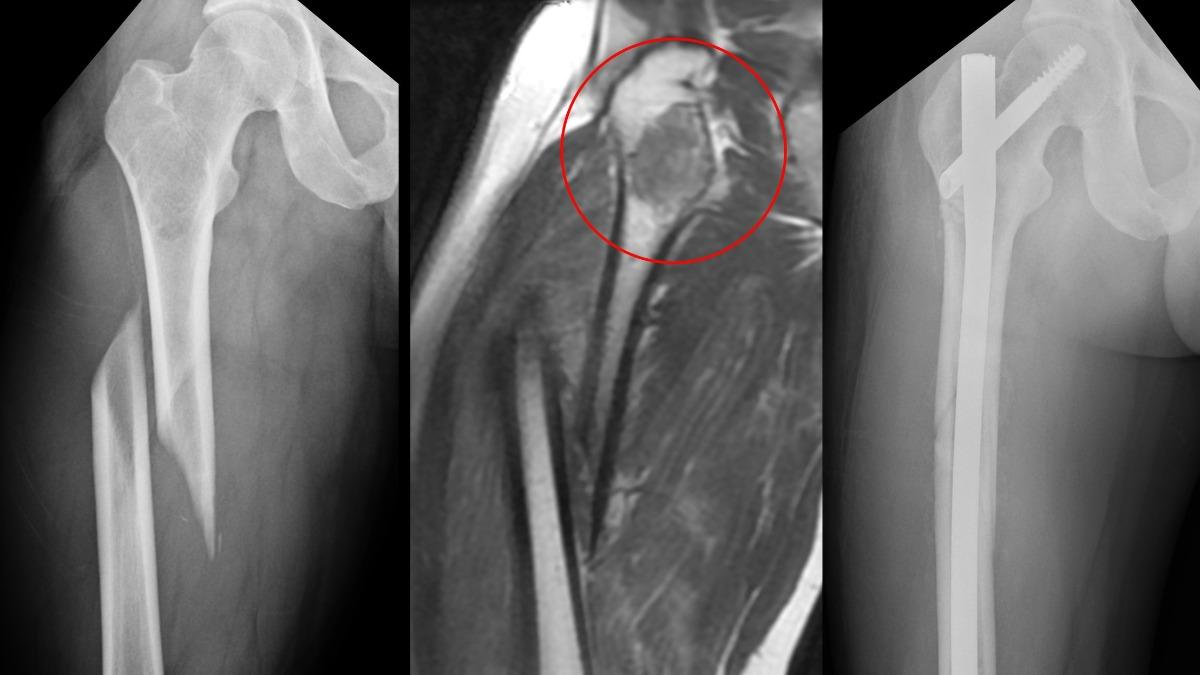

台中市一名30歲的李姓男子,2025年底到日本滑雪時慘摔,由於撞擊力道強烈,李男當場大腿變形,不過緊急送醫檢查後,日本當地醫院發現李男大腿骨中段有6公分骨腫瘤,但由於腫瘤性質不明,李男只能打上鋼架飛回台灣的光田醫院,尋求骨科部部長楊鎮源接手,楊鎮源說明,許多骨骼疾病初期症狀並不明顯,常被誤認為一般運動傷害,對於李男的治療策略,必須兼顧處理骨折與腫瘤,好在手術相當順利,李男已能使用輔具正常行走。